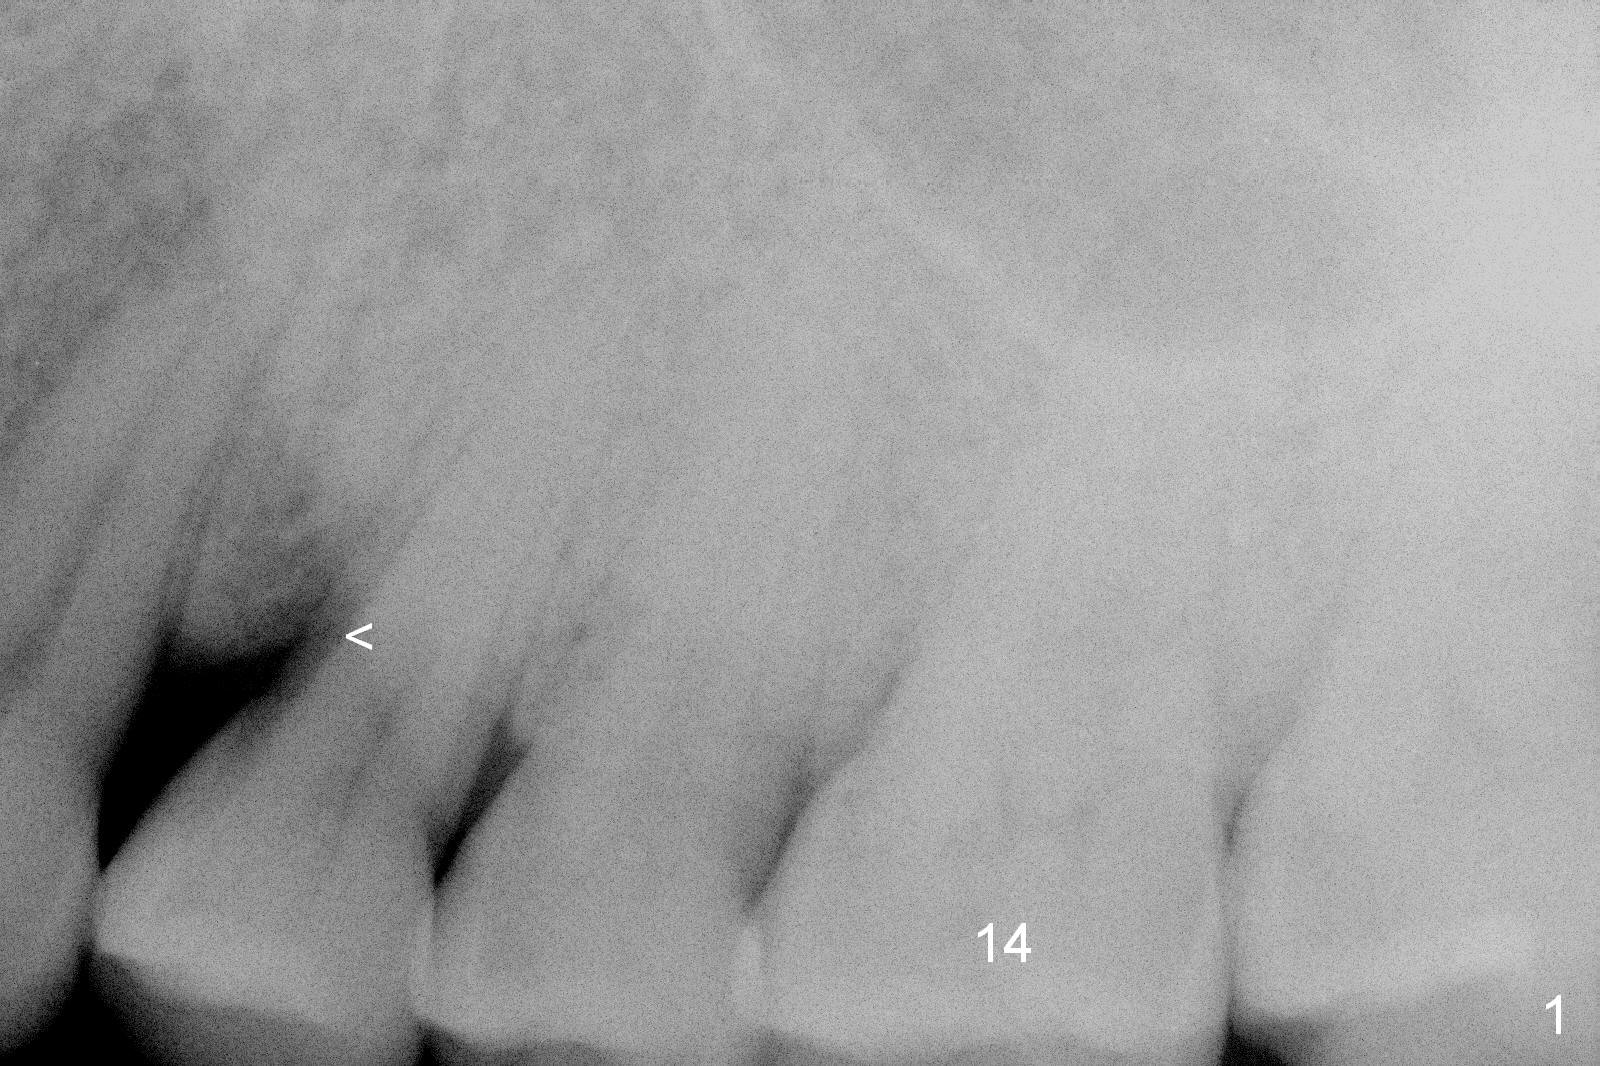

A 54-year-old lady has history of chronic periodontitis, characterized by bone loss (Fig.1 <, 2) . Her oral hygiene is fair. Bone loss and obliterated canals at #14 (Fig.1) are apparently related to bruxism. The latter seems to cause crack tooth at #15 with infection lately (Fig.3). Since the bone height is plenty (Fig.4), the longest implant will be used (5-7x20 mm (tissue-level) or 5.5x13 mm or longer (bone-level, Fig.5)). Use 2 mm drill to measure the socket (Metronidazole) depth and osteotomy will be at least 6 mm in the new bone. In fact, the tooth #14 is found to be affected when the patient returns from a periodontist's office (Fig.3).